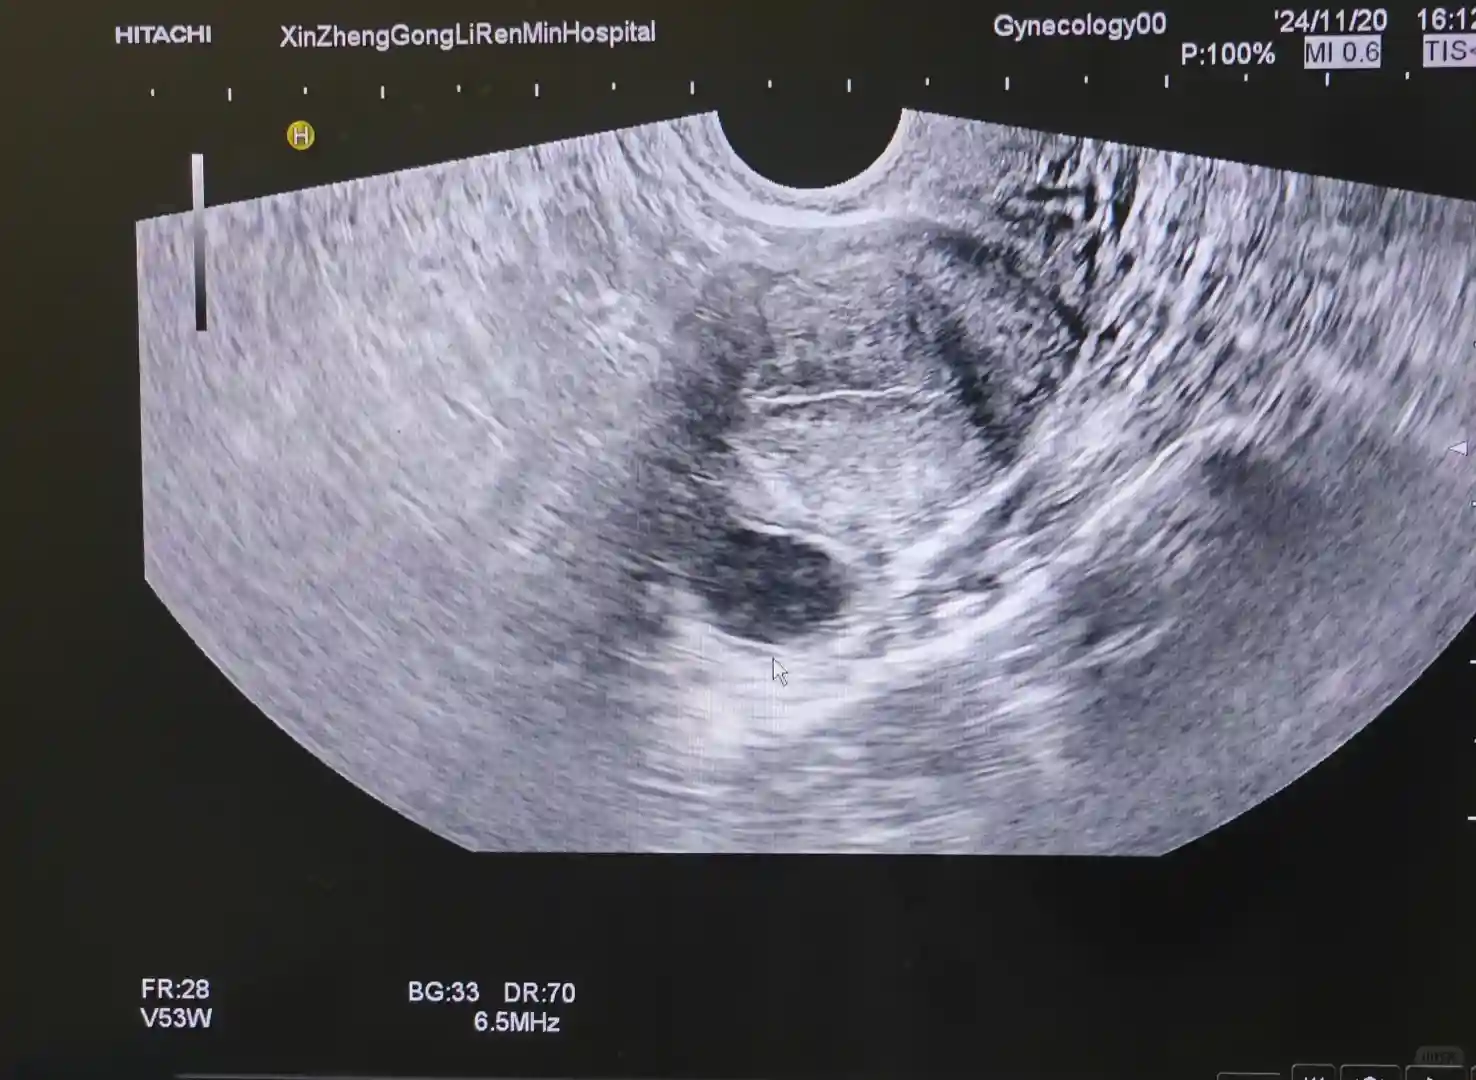

11.20 D13 下午四点监测卵泡,左侧22*16,右侧无,内膜8,当天没有打破乱针,晚上蹦蹦跳跳1小时;

11.21 D14 早上监测发现卵泡已排出,盆腔积液21*6.8,中午紧急安排一次;11.22 D15 早晚各一颗黄体酮胶囊,50mg,连吃10天,停培坤丸,继续吃滋肾育胎丸;